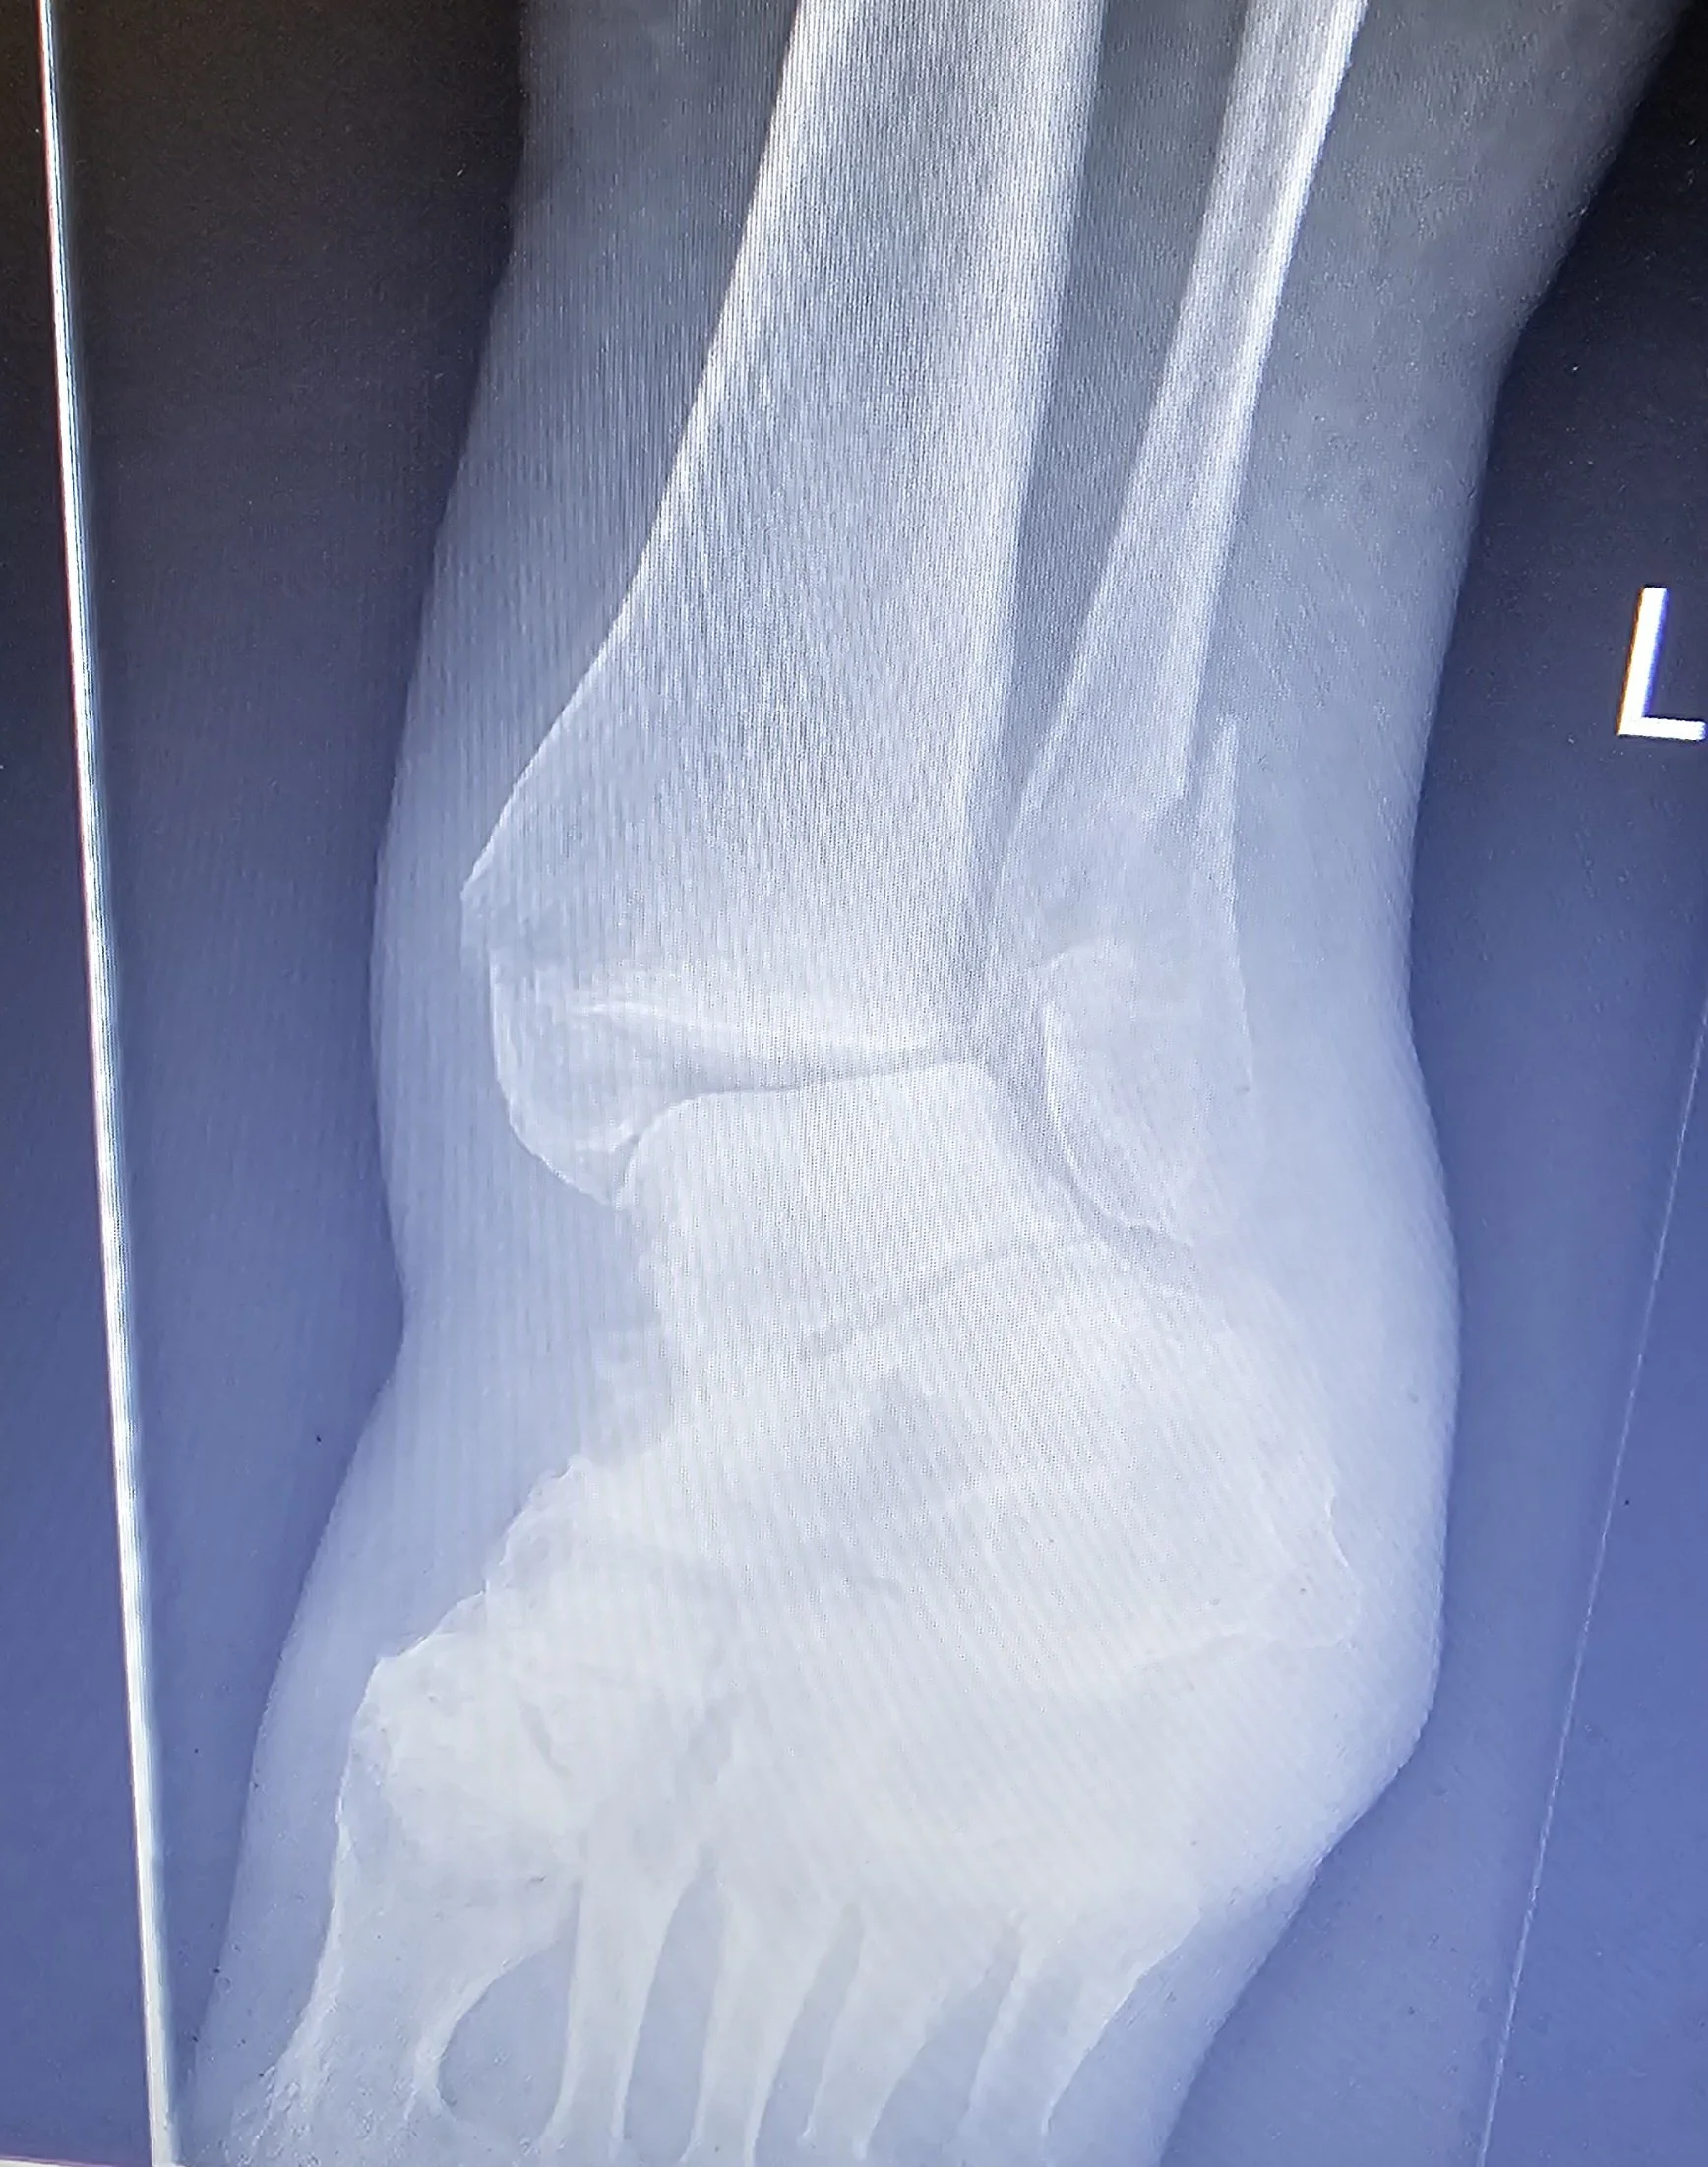

Ankle and Foot Fractures

Physiotherapy for Ankle and Foot Fractures

Ankle and foot fractures can significantly limit mobility, weight-bearing and daily function. Whether managed surgically or non-surgically, physiotherapy plays a crucial role in restoring strength, movement and confidence once your fracture is stable and cleared for rehabilitation. Our physiotherapists specialise in guided, evidence-based recovery for all types of ankle and foot fractures, including avulsion fractures, ensuring safe progression through each stage of healing.